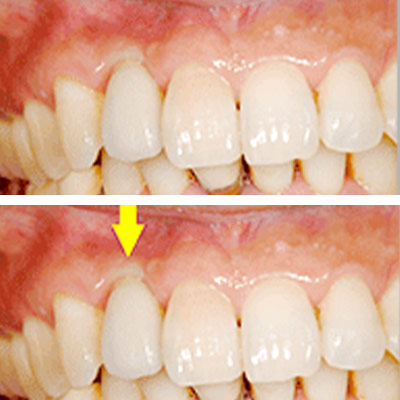

もう少し長くなっていますが、口唇を上に引っ張らない限りはそれが見えません。

-

一見それほど問題にならない程度には仕上がっていますが、隣の歯との間、歯肉の間に空間が残っており、中にはご満足いただけないこともあります。幸いにして、この患者様方には、あらかじめ、見た目についてのご説明をさせていただいた上で、治療を始めていますので、ご納得いただいております。

審美性をさらに高め、天然歯とまったく区別ができない様にしようと思えば、追加の費用をいただいて、歯肉の移植術を行なうなど、方法はありますが、その患者様のお考えになるレベルが様々で、ご満足いただけない場合もあり、当院では、非常に高度な審美性はお約束できないと、ご説明させていただいています。